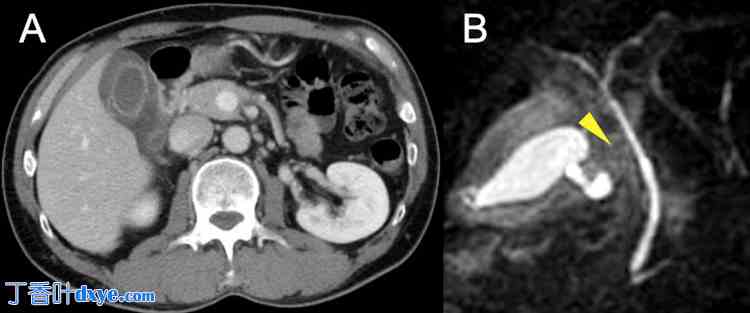

CT 影像显示胆囊向内侧移位,并伴有明显的胆囊壁水肿(图 1)。

图 1. 病例 1 胆囊扭转的放射学表现。

(A) 轴向 CT 图像显示胆囊向内侧移位,并伴有明显的胆囊壁水肿(黄色箭头)。

(B) 冠状 CT 图像显示胆囊向内侧移位并伴有明显的胆囊水肿(黄色箭头)。